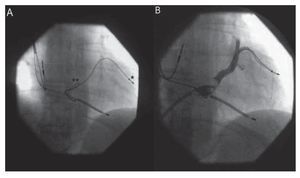

Por la vena femoral derecha se introdujo un catéter de ablación Marinr (Medtronic, Minneapolis, Estados Unidos) en la aurícula derecha a través de una vaina larga SR0 de DAIG (DAIG, St. Jude Medical, Estados Unidos) que se dirigió hasta el SC tras haber introducido la porción distal del catéter de ablación en su porción distal a modo de guía. Retirado el catéter, se realizó una angiografía para reevaluar la anatomía del SC con vistas al recambio (fig. 1). Tras ello, se retiró el sistema a la aurícula derecha y, con la punta del catéter de ablación máximamente curvada, se enganchó el electrodo, y se realizó una ligera tracción de éste hacia la vena cava inferior (fig. 2). El electrodo se movilizó sin dificultad, con desaparición inmediata de la estimulación frénica. El umbral de estimulación final fue de 2,4 V a 0,5 ms. Dada la inminencia del recambio del generador, decidimos no colocar un stent de sujeción, ya que podría dificultar la manipulación del electrodo en el caso de que el resultado obtenido fuese transitorio.

Fig. 1. A: posición del electrodo en el seno coronario (SC) (*) en posición oblicua derecha antes de la recolocación, con vaina larga en SC (**). B: angiografía del SC.